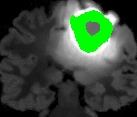

In Fig. 12, we show several tumor segmentation results for all data types.

In Table II, we compare results obtained using different descriptor structures:

patch-based [48], superpixel-based [54],

and superpatch-based (= pixels).

We use the Dice coefficient [55] as evaluation metric,

measuring the overlap between the automatically segmented structure and the ground truth.

The superpixel-based approach

appears very limited since it fails at capturing the tumor context and their location in other images.

Regular patches are also limited in this context, due to the variations in the structure shapes.

Superpatches provide a robust descriptor, since they follow image intensities and capture the superpixel neighborhood,

leading to more accurate segmentation.

These experiments demonstrate that superpatches within the SPM framework provide fast and accurate segmentation results

even on non-registered multi-modal images with poor resolution.